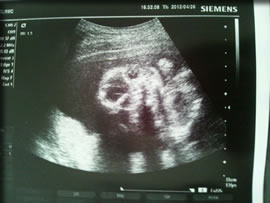

4月26日 検診(19w5d)☆

性別まだ分かりませんでした

旦那ちゃんには一瞬おちんちんらしきものが見えたらしいんだけど、ほんとかな?( ̄ー☆

でもそぉ言われてみれば写真のカリンちゃん、目元が旦那ちゃんに似てて男の子っぽいよぉな

19w5d